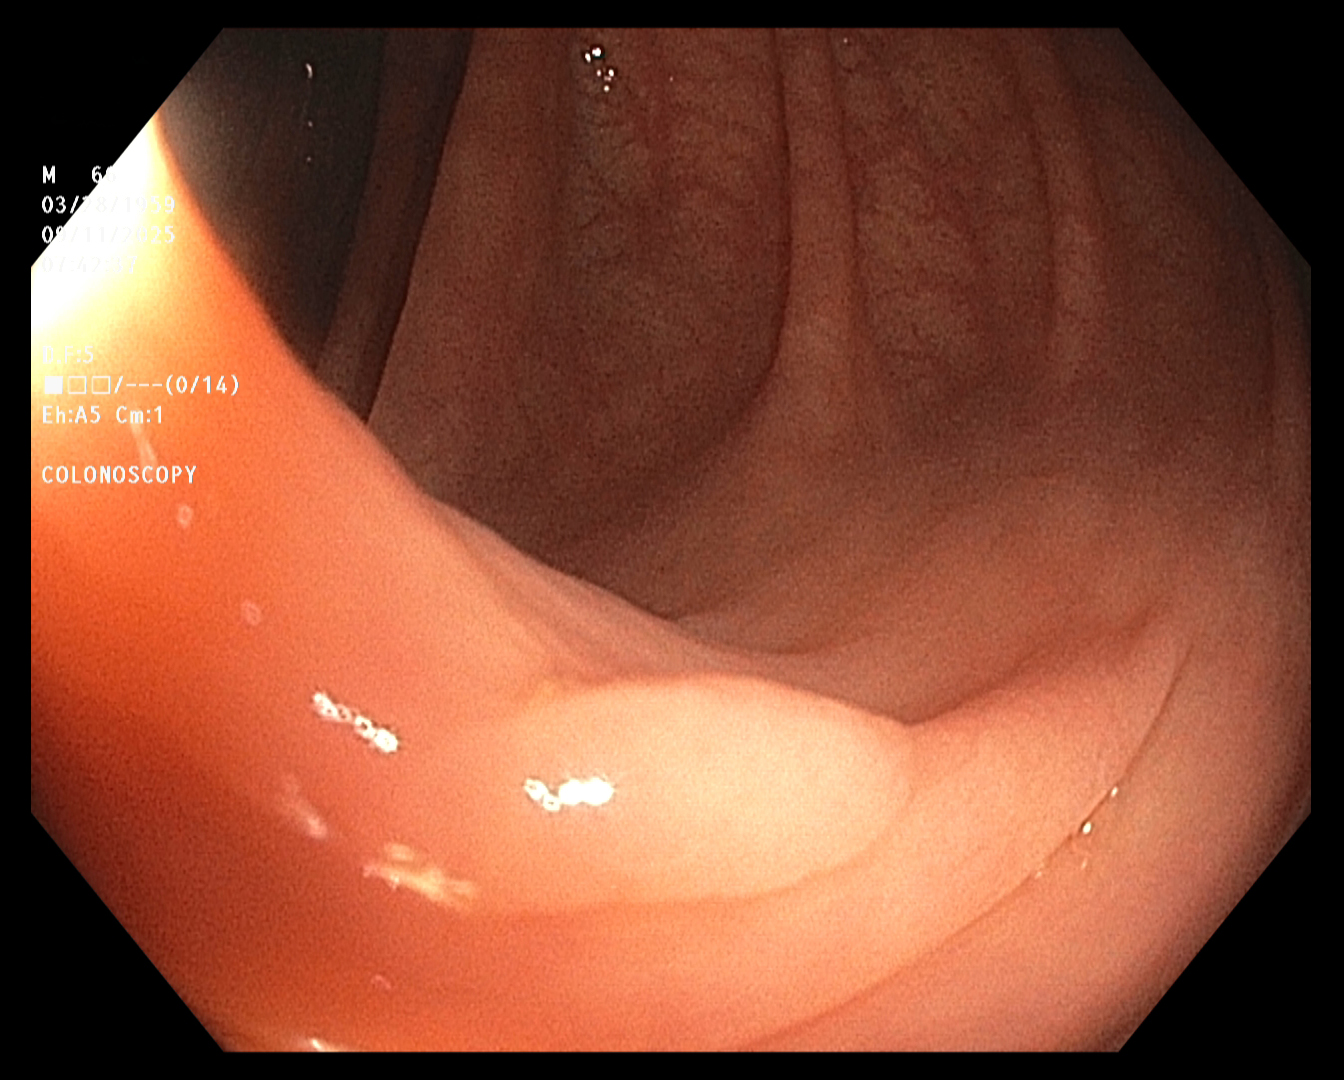

The endoscopist in this study generated a series of images showing the cecum and several sites

of concern (e.g., polyps). The cecum is the beginning of the colon, so reaching it ensures that

the entire colon will be examined. The endoscope was slowly withdrawn, while the endoscopist

assayed mucosal detail and identified and removed several polyps for later examination. The

first and last images were taken about twenty minutes apart.

Cecum